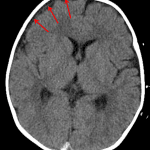

- Thin hyperdense collection overlying the posterior right parietal lobe and posterior interhemispheric falx, concerning for acute subdural hematoma

- Thin CSF density collection overlying the right frontal convexity, which may represent a chronic subdural hematoma vs hygroma

- Non-accidental trauma

Constellation of findings raises the question of nonaccidental trauma:

Thin hyperdense collection measuring up to 2 mm overlying the posterior right parietal lobe and posterior interhemispheric falx, concerning for acute subdural hematoma. No significant mass effect, herniation, or hydrocephalus.

Thin CSF density collection overlying the right frontal convexity, which may represent a chronic subdural hematoma vs hygroma.